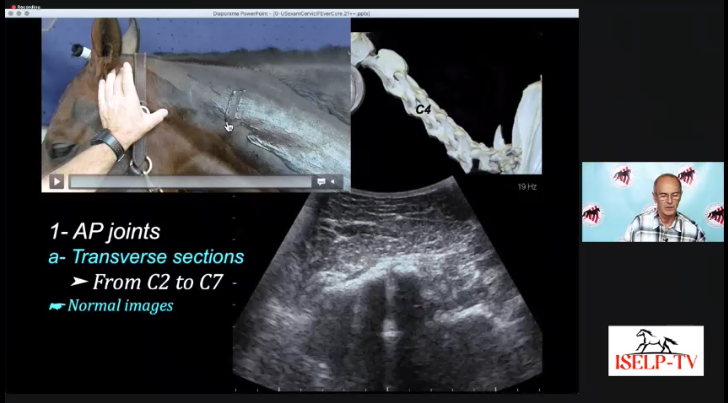

11:00am - Dr. Erik Bergman - Lecture - "The Cranial Neck (ab)Normal Findings"